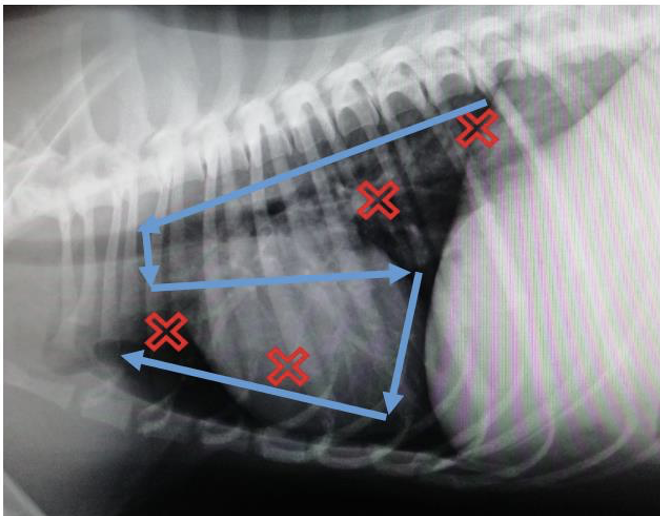

What is VetBLUE?

A

Veterinary bedside lung ultrasound exam

Allows assessment of lung parenchyma & pleural space

4 point scan on both sides of chest (red X’s)

13

Q

What is PLUS?

Pleural lung ultrasound

Addition to VetBLUE

sweep ‘S’ across lung fields (blue lines)

9 points in total on both sides of chest